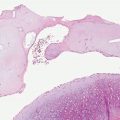

In CL, there is a dense mixed dermal inflammatory infiltrate predominantly of histiocytes, lymphocytes, and plasma cells (Fig. 24-3). Giant cells and eosinophils may also be seen, and neutrophils are noted once ulceration has occurred. Parasitized histiocytes are appreciable within the inflammation (Fig. 24-4A, B) (53–55). In early lesions, there may be overlying acanthosis or atrophy. In later lesions, ulceration and pseudoepitheliomatous hyperplasia may develop, and organisms may be difficult to find due to decreased numbers. There is an increase in the number of tuberculoid granulomas, but perineural involvement and caseating necrosis are rarely seen (56,57). Tuberculoid granulomas are prominent in recidivous or lupoid disease.

Figure 24-3 Leishmaniasis. Low-power view of ulcerated lesion of CL with dense mixed inflammatory infiltrate.